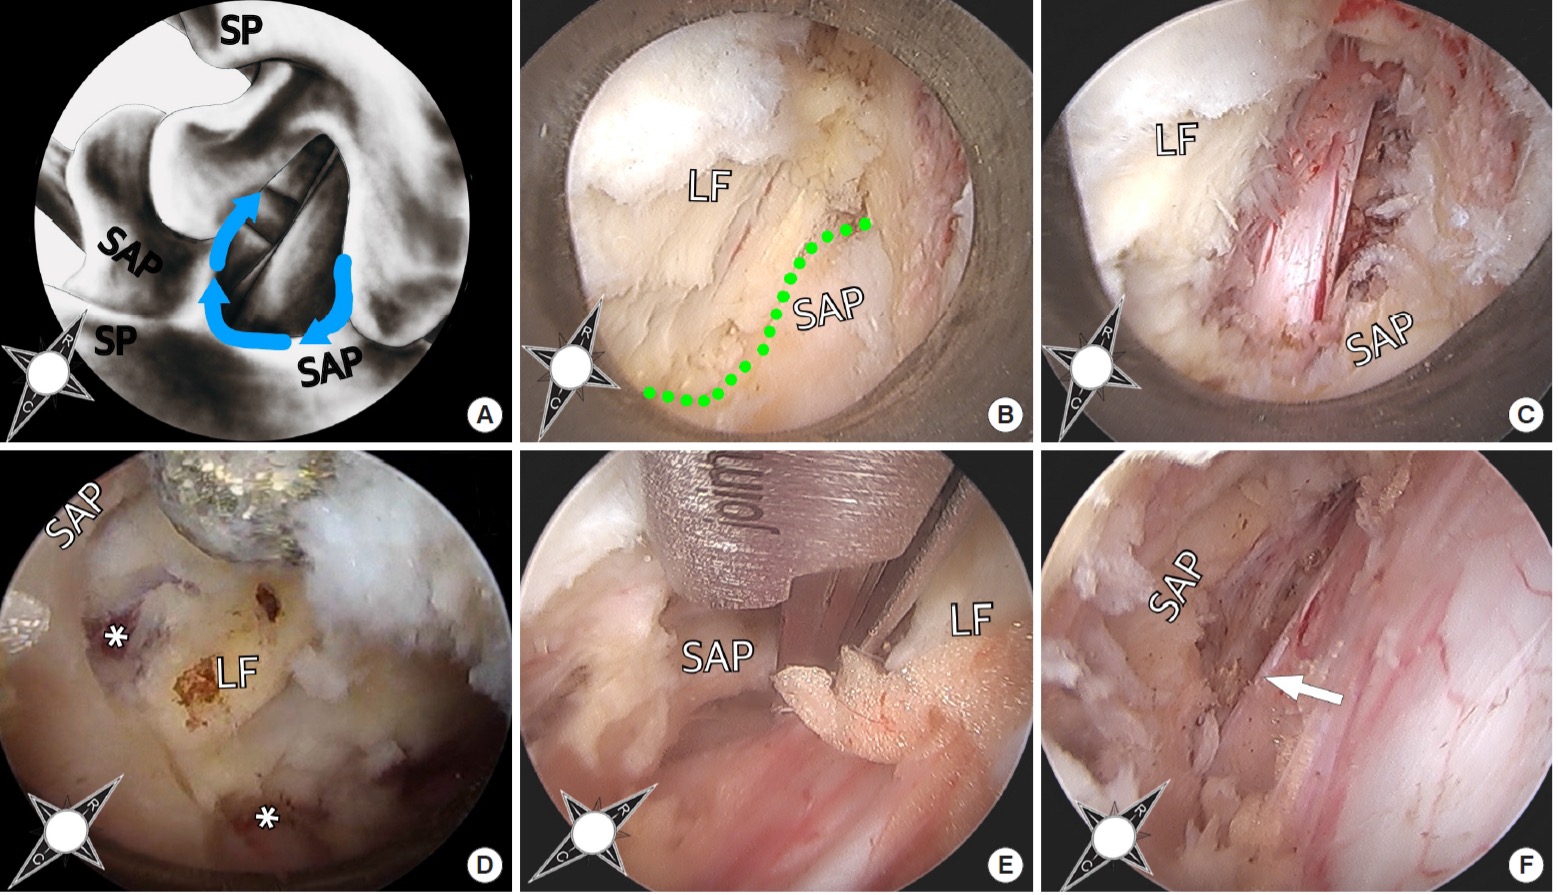

A anatomia endoscópica é aquela observada diretamente durante a cirurgia endoscópica da coluna, através da câmera inserida no portal cirúrgico.

Aqui, o cirurgião vê a estrutura ao vivo, com ampliação e iluminação intensificada.

A perspectiva muda completamente:

• Em vez de cortes axiais ou sagitais, o cirurgião vê a anatomia em profundidade.

• Os marcos anatômicos são identificados de forma dinâmica, sob movimento.

• Estruturas como ligamento amarelo, disco herniado, facetas e raízes nervosas ganham textura, profundidade e comportamento real.

O que a visão endoscópica acrescenta?

• Ampliamento natural da imagem

• Percepção tridimensional pelo movimento dos instrumentos

• Identificação precisa de variações anatômicas

• Visualização da relação real entre disco, raiz nervosa e estruturas ósseas

• Possibilidade de observar sangramentos, pulsações e tensões teciduais

Essa experiência visual muda completamente a maneira como o cirurgião compreende a coluna.